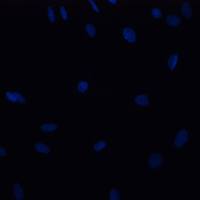

相关实验:双氧水诱导肿瘤细胞凋亡

双氧水诱导肿瘤细胞凋亡的检测

ID2250 DAPI 热点染料/探针 索莱宝